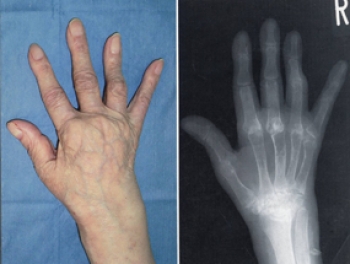

主に手足の関節を侵し、これにより関節痛、関節の変形もしくは破壊が現れます。

関節の変形や滑膜の細胞が増殖したり、軟骨の破壊が始まる。その後、関節も破壊し、関節は動かなくなってしまいます。

手の指の関節、第2関節(PIP)、第3関節(MP)が特に侵されます。また、手首や足の指、肘、膝など体の中心に近い大きな関節の痛みが出てくることもあります。

指の変形がひどくなると

スワンネック変形(白鳥の首状の変形)

ボタン穴変形

尺側偏位(指の全てが外側を向く変形 になります

レントゲン検査で典型的な関節所見

レントゲン